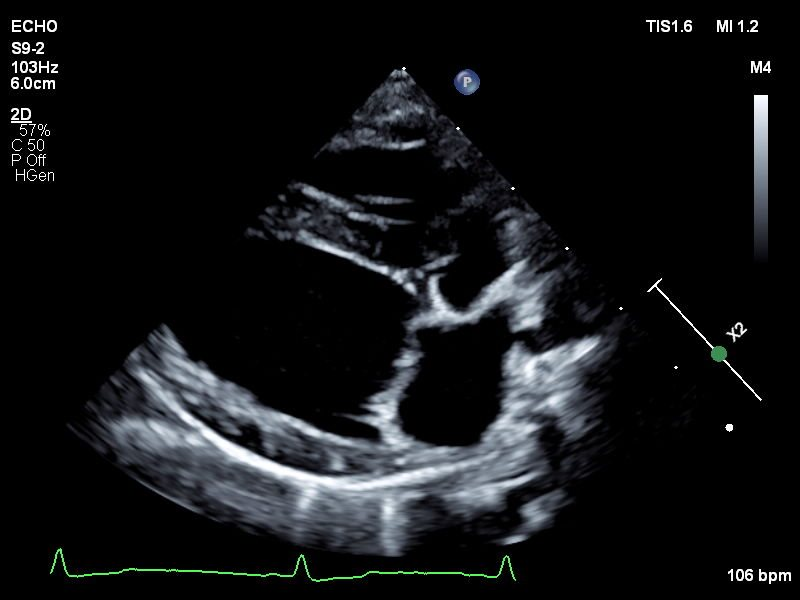

Echocardiograms

Veterinary echocardiography is a type of ultrasound imaging that focuses on the heart.

Echocardiography assesses the structure and function of an animal's heart. This non-invasive

procedure employs ultrasound technology to produce detailed, real-time images of the

heart's chambers, valves, and blood flow. Echocardiography is essential for diagnosing

and monitoring heart conditions such as heart murmurs, cardiomyopathy, and valve disorders.